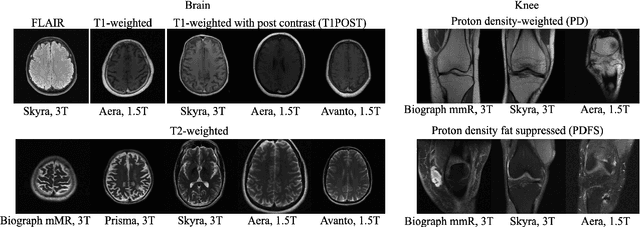

Abstract:Deep learning based methods for image reconstruction are state-of-the-art for a variety of imaging tasks. However, neural networks often perform worse if the training data differs significantly from the data they are applied to. For example, a network trained for accelerated magnetic resonance imaging (MRI) on one scanner performs worse on another scanner. In this work, we investigate the impact of the training data on the model's performance and robustness for accelerated MRI. We find that models trained on the combination of various data distributions, such as those obtained from different MRI scanners and anatomies, exhibit robustness equal or superior to models trained on the best single distribution for a specific target distribution. Thus training on diverse data tends to improve robustness. Furthermore, training on diverse data does not compromise in-distribution performance, i.e., a model trained on diverse data yields in-distribution performance at least as good as models trained on the more narrow individual distributions. Our results suggest that training a model for imaging on a variety of distributions tends to yield a more effective and robust model than maintaining separate models for individual distributions.